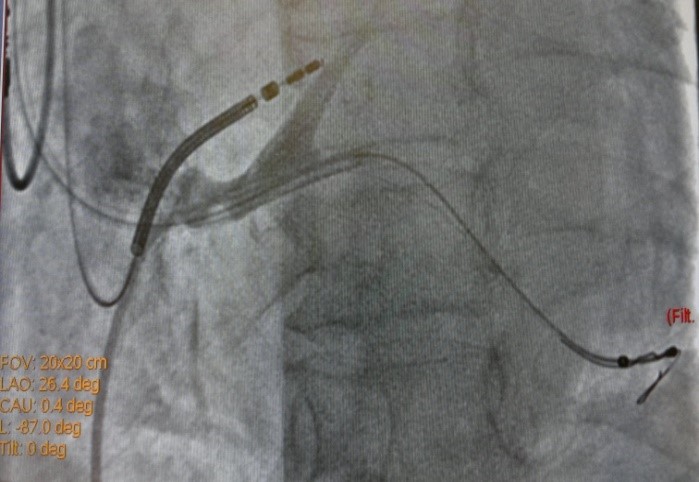

19.08.2015 выполнена попытка имплантации СРТ-D устройства, имплантировать ЛЖ электрод в заднею вену сердца не представилось возможным ввиду многократных смещений ЛЖ электрода в КС. Через 7 дней, вторым этапом, аритмологами и ренгенхирургами принято решение о имплантации ЛЖ электрода в заднюю вену ЛЖ с фиксирующим стентированием ЛЖ электрода в задней вене ЛЖ. Под м/а выполнен разрез в левой подключичной области по п/о рубцу. Выделен и выведен в рану ИКД. Пунктирована подключичная вена из раны. Желудочковый дефибриллирующий электрод активной фиксации позиционирован и вкручен в область МЖП 15 мV (с целью достаточного межэлектродного расстояния) [3], порог стимуляции желудочков 0,8 мА. В ПП по системе доставки доставлен катетер для КС, установлен в КС. Выполнена ангиография коронарного синуса (рис.1) – доступна единственная задняя вена ЛЖ, размером более 4 мм. ЛЖ электрод заведен через систему доставки и установлен в заднюю вену ЛЖ по коронарному проводнику. Порог стимуляции ЛЖ-2.0 мА, порог чувствительности 16.6 мВ. Стимуляции диафрагмального нерва нет. При попытке удаления системы доставки, последний дислоцируется в КС. Множественные попытки имплантации ЛЖ электрода безуспешны в связи с дислокацией последнего. При имплантации в дистальное русло порог ЭКС >6мА. ЛЖ электрод установлен в дистальное русло ЗВЛЖ по коронарному проводнику. Принято решение о фиксирующем стентирование ЛЖ электрода в ЗВЛЖ. Под м/а пунктирована v.f.s., установлен интродьюсер 6 Fr. К устью КС подведен проводниковый катетер JR4 6FR. В дистальное русло ЗВЛЖ проведен коронарный проводник (рис.2). По проводнику в ЗВЛЖ заведен стент 4.5-16 mm, выполнена имплантация (рис.3). При контрольной ангиографии диссекций не выявлено, стент расправлен полностью. Под контролем Rg-скопии и на раздутом баллоне удалена система доставки ЛЖ электрода, ЛЖ электрод стабилен (рис.4), порог ЭКС-0.8 мА (до стентирования 1,5 мА), сенсинг 10 мВ. Электроды фиксированы в ране. Подключен CRT-D и помещен в прежнее ложе над грудными мышцами. На ЭКГ эффективная бивентрикулярная стимуляция.

Рис.2. Рентгеновский стоп-кадр при контрастирование коронарного синуса и проведение коронарного проводника в «целевую» вену.